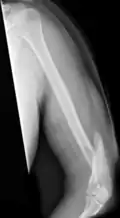

Midshaft humerus fracture with callus formation

Fractures of the humerus shaft are most often uncomplicated, closed fractures that require nothing more than pain medicine and wearing a cast or sling. For midshaft fractures up to 12 weeks may be required for healing.[17]

In most cases, people are discharged from an emergency department with pain medicine and a cast or sling. These fractures are typically minor and heal over the course of a few weeks.[4] Fractures of the proximal region, especially among elderly people, may limit future shoulder activity.[19][20] Severe fractures are usually resolved with surgical intervention, followed by a period of healing using a cast or sling.[11] Severe fractures often cause long-term loss of physical ability.[21] Complications in the recovery process of severe fractures include osteonecrosis, malunion or nonunion of the fracture, stiffness, and rotator cuff dysfunction, which require additional intervention in order for the patient to fully recover.[21]